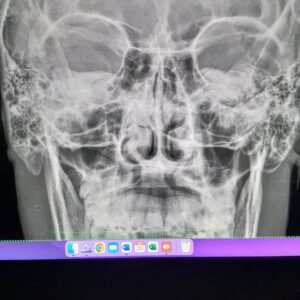

La que le están por hacer sale $400.000

Y las otras 2 al rededor de 6 millones de pesos